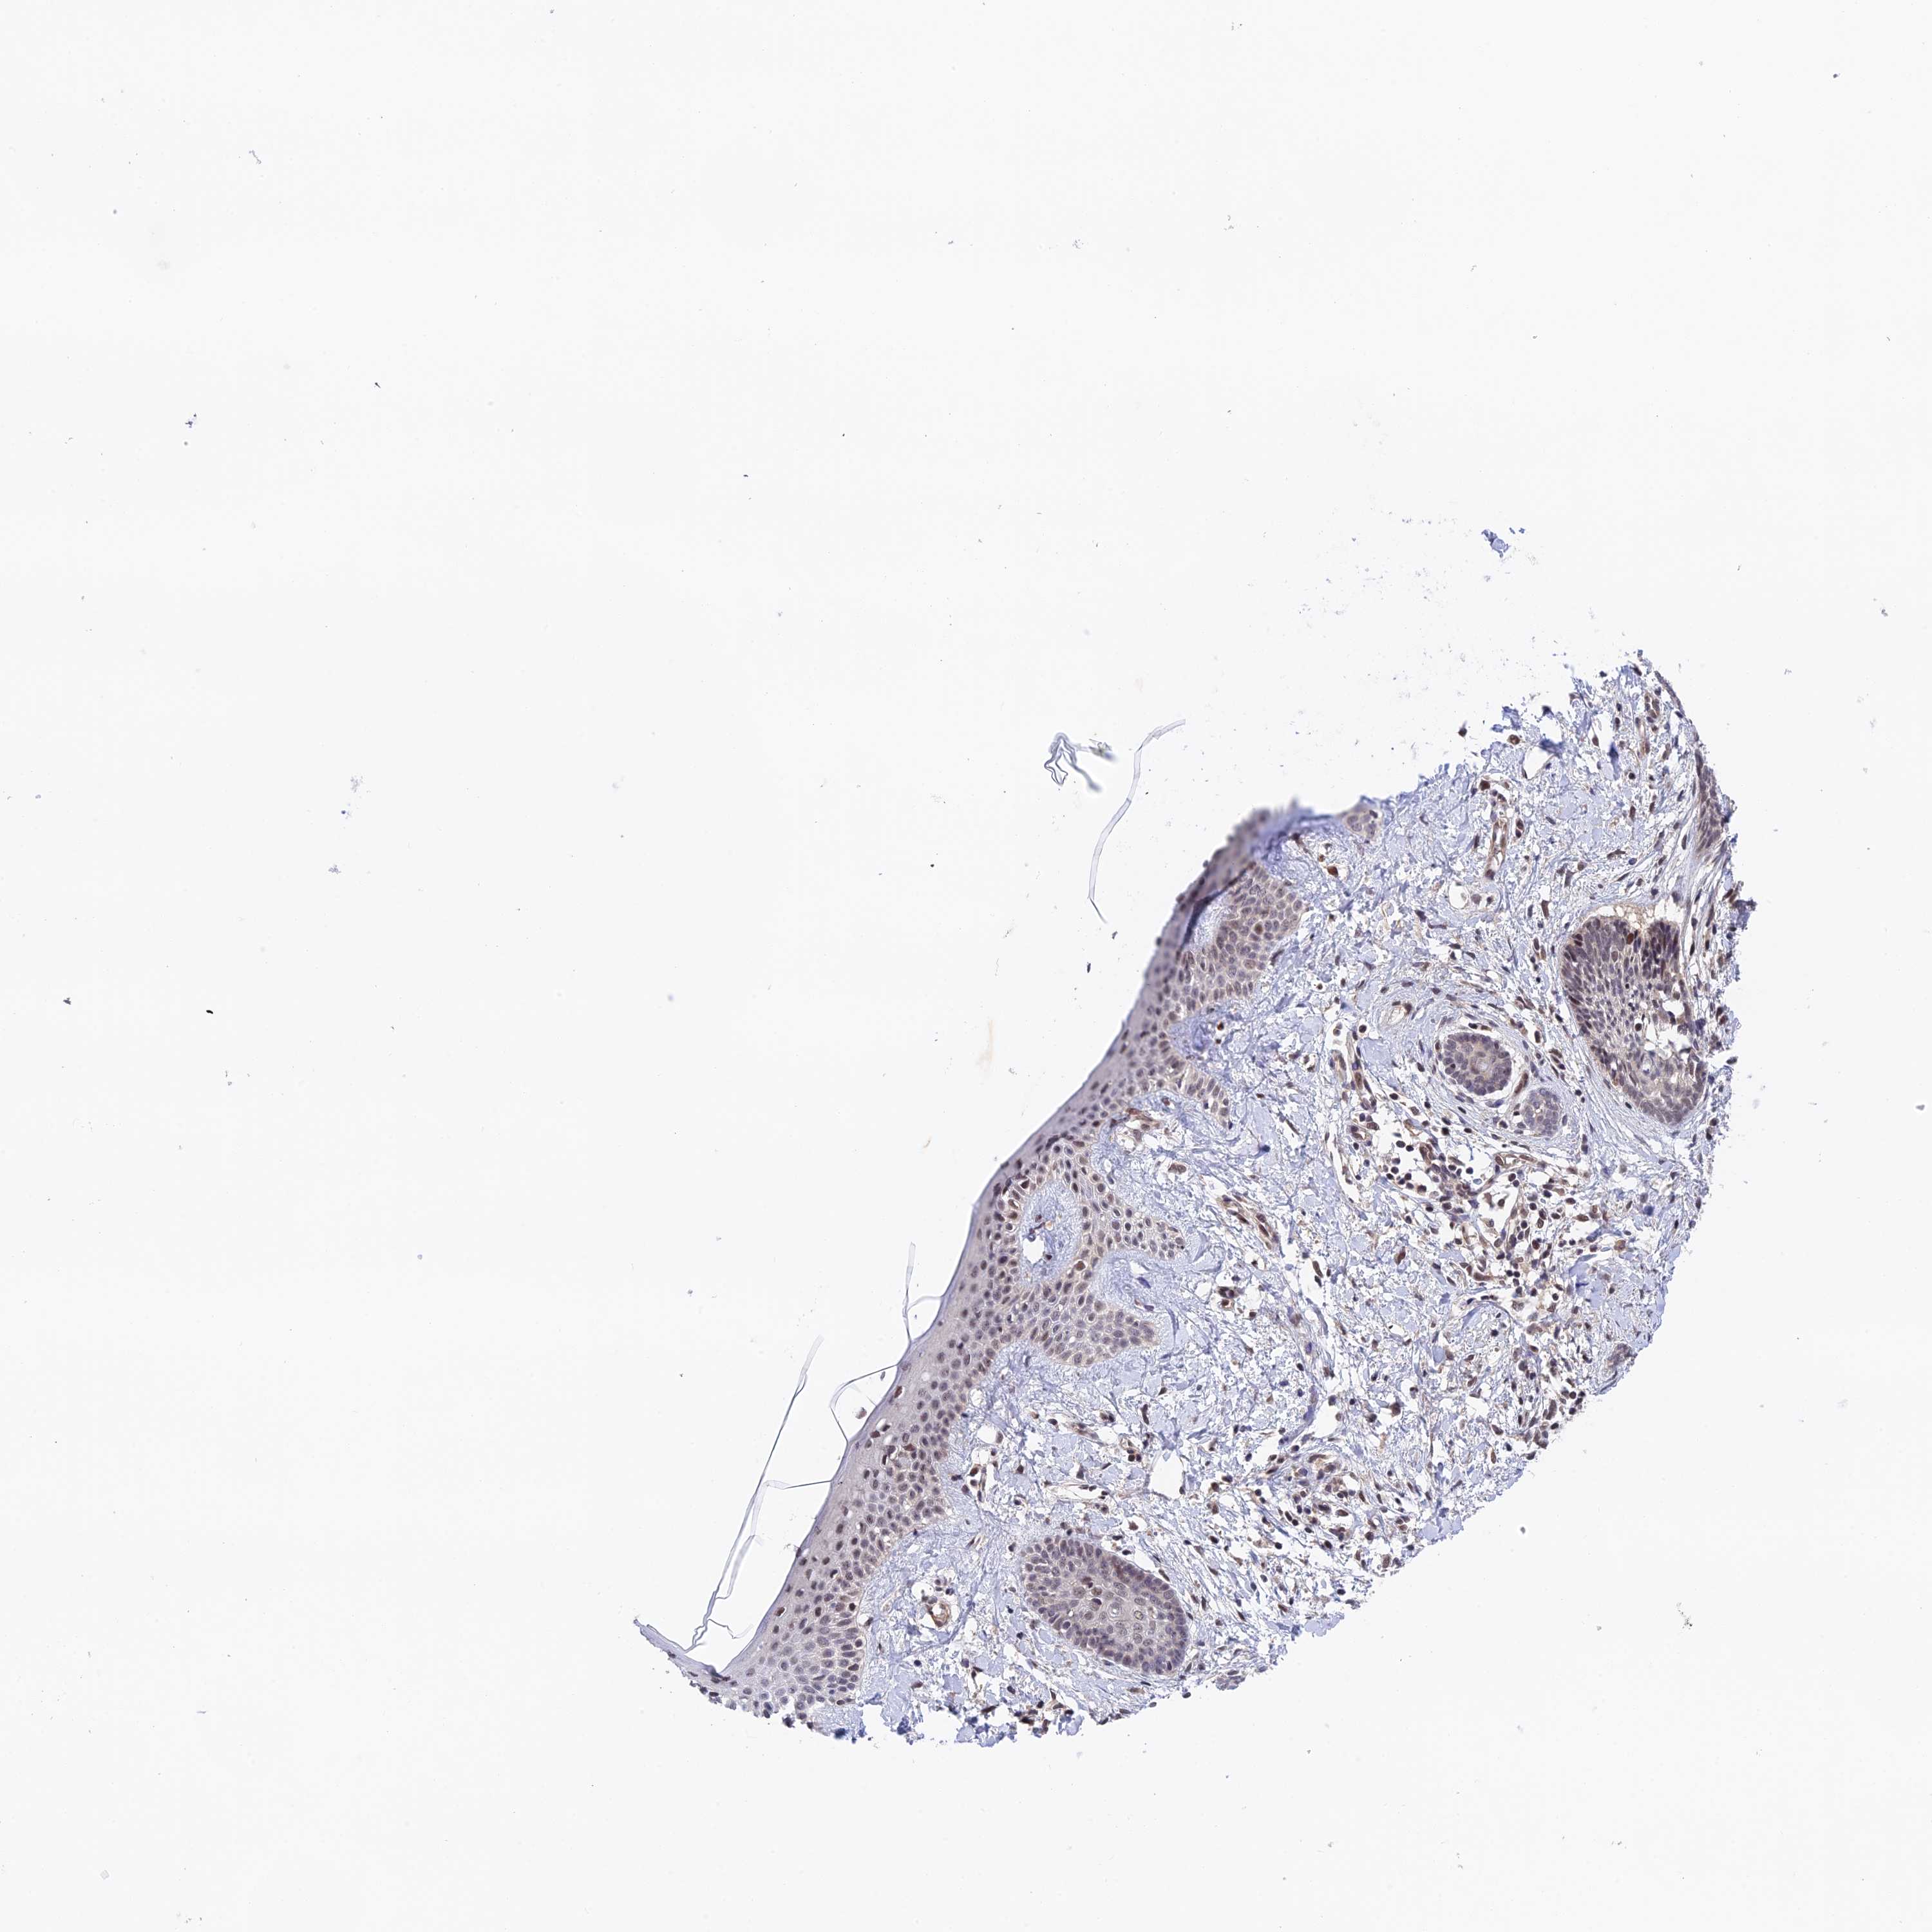

Basal cell and squamous cell cancer

SKIN CANCER - Protein expressioni

A mouse-over function shows sample information and annotation data. Click on an image to view it in a full screen mode. Samples can be filtered based on level of antibody staining by selecting one or several of the following categories: high, medium, low and not detected. The assay and annotation is described here.

Each image is clickable and will lead to virtual microscopy that enables deeper exploration of all samples and also displays staining intensity scores, fraction scores and subcellular localization as well as patient and tissue information for each sample.

Squamous cell carcinoma, NOS